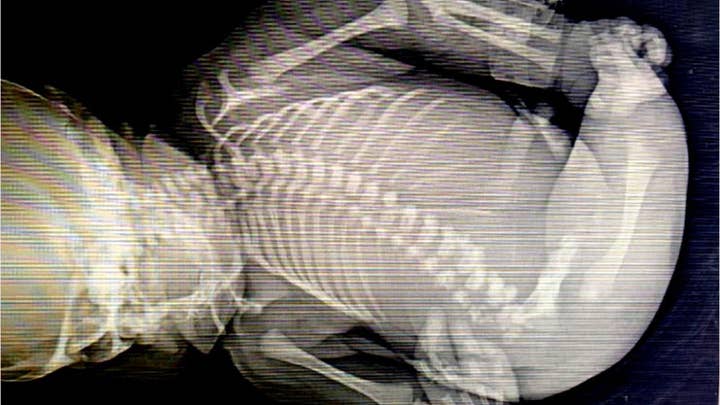

The parents of a baby who died minutes after being born with a rare condition, in which the legs are either partially or completely fused together, have donated their child's body to research.

The baby, who reportedly could not be assigned a gender due to the condition, was diagnosed with sirenomelia, also referred to as "mermaid syndrome."

Born on Monday at a hospital in India, the baby died just 15 minutes after birth due to breathing issues, SWNS reported. The parents, who were not identified, reportedly knew that their child would have congenital issues, but did not know about sirenomelia.

Bansode said only 300 cases of the syndrome have ever been documented.

The exact cause of sirenomelia is unknown, according to the National Organization of Rare Diseases (NORD). It is often fatal during the newborn period and is associated with severe life-threatening complications.

"Babies with mermaid syndrome do not live more than 24 or 48 hours," Bansode said. "We are in the process of preserving the infant's body. The baby's parents have donated the body for research purpose for medical students."